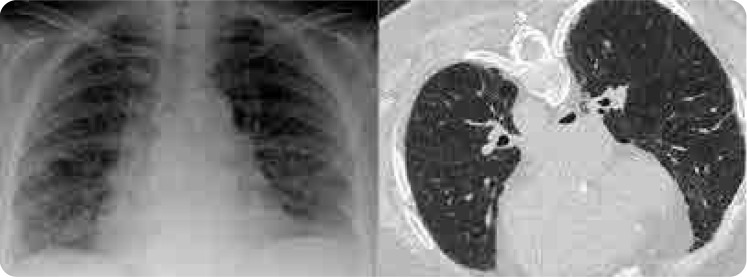

Case: A 65-year-old female patient with rheumatoid arthritis (RA) presented with shortness of breath and a non-productive cough after 15 years of stable MTX treatment. Chest X-ray revealed bilateral ill-defined infiltrates, and high-resolution computed tomography (HRCT) showed diffuse ground-glass opacities. All diagnostic tests for infection were negative. Suspecting MTX-associated HP, MTX was discontinued, leading to significant clinical improvement.